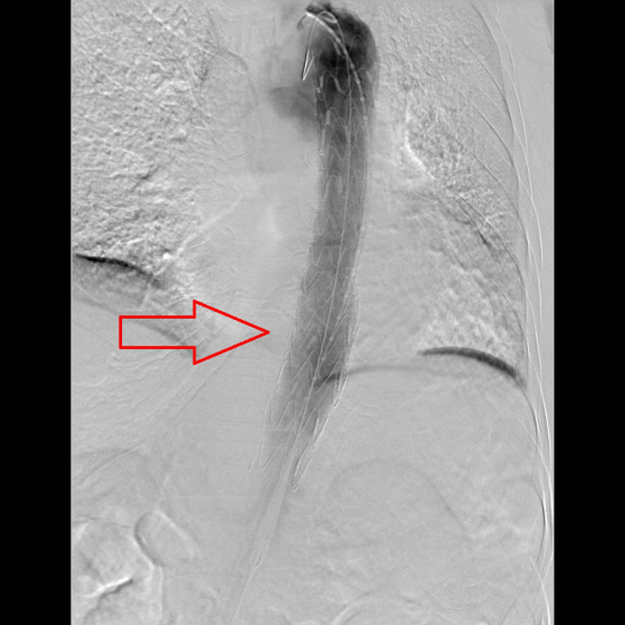

(术后,林老伯体内巨大的动脉瘤已消失,破裂口被封闭)人体“不定时炸弹”——主动脉瘤

如果说主动脉瘤的传统开腹手术属于重拳巨创,很多患者无法耐受,为手术期死亡率高;那么腔内隔绝术治疗主动脉瘤可以认为是微创,几乎所有的患者都可以耐受,加上最近使用各种器官保护药物和造影用的肾脏保护造影剂,更加降低了腔内隔绝术的风险性。很多患者在腔内隔绝术后第2天,就可以下床活动,5天就可以出院。可以说,腔内隔绝术治疗主动脉瘤不仅是血管外科技术的革命,也是扩大主动脉瘤治疗人群的革命。腔内隔绝术给每一位主动脉瘤患者带来了福音。(邓敏婕)